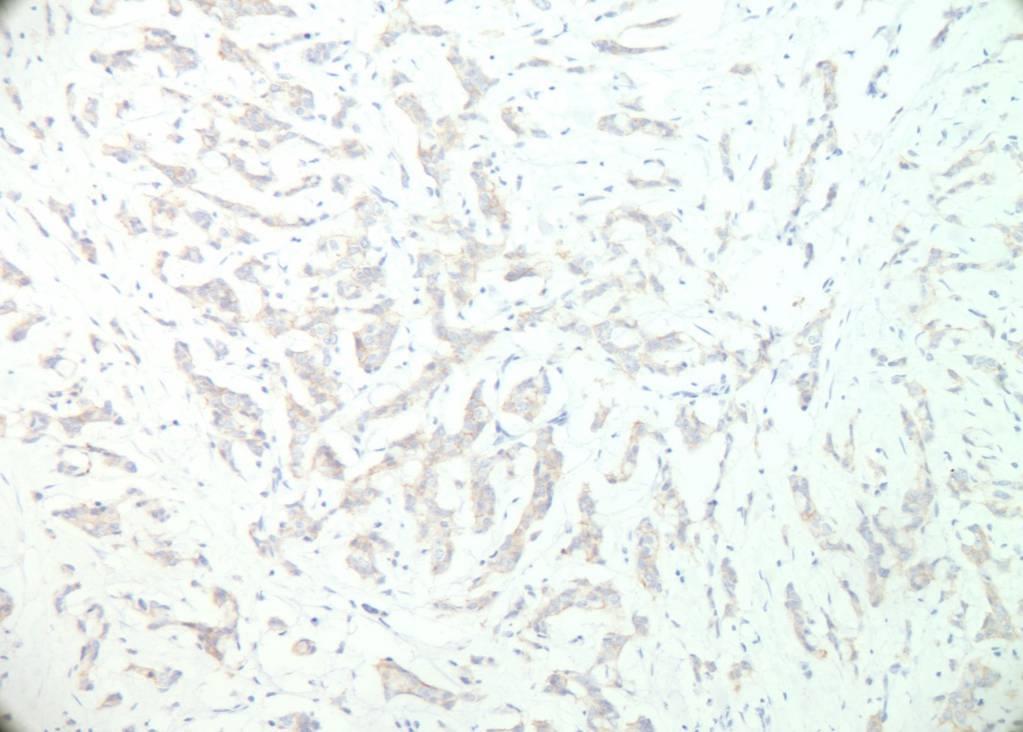

by IHC001

Her2 immunohistochemistry assesses HER2 protein overexpression. A 2+ score requires further testing by FISH for gene amplification.

Only membrane staining of the invasive tumour should be considered when scoring the IHC tests. If a commercial kit assay system is used, it is recommended that laboratories adhere strictly to the kit assay protocol and scoring methodology. Local modifications of techniques can lead to false positive and negative assay results.

0 Negative No staining/incomplete membrane staining in < 10% cells 1+ Negative Faint/barely perceptible incomplete membrane staining in >10% cells 2+ Borderline weak to moderate complete membrane staining in >10% cells 3+ POSITIVE Strong and complete membrane staining in more than 30% tumour cells.

1+ 2+